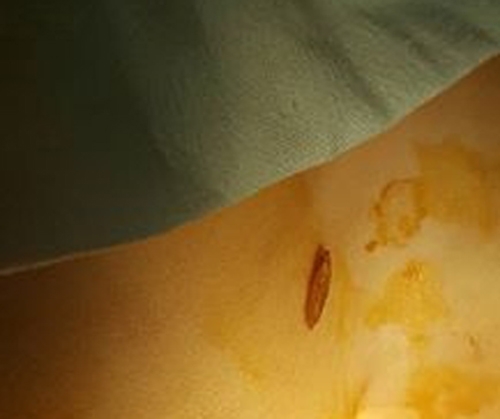

Ngày 18/9, Bệnh viện Phụ Sản Hà Nội đã tiếp nhận và điều trị thành công một bệnh nhi 18 tháng tuổi bị rơi hạt thóc vào trong âm đạo. Sự việc khiến đã khiến người nhà bệnh nhi hoang mang và lo lắng.

Sau đó, gia đình đã cố gắng lấy hạt bằng các biện pháp nhưng vô tình đẩy hạt thóc vào sâu trong âm đạo của bé hơn. Bé cũng được đưa đến bệnh viện tuyến huyện, tỉnh nhưng việc lấy dị vật ra không thành công.

| Hạt thóc được lấy ra từ âm đạo của bé 18 tháng tuổi. |

Theo BS Lê Thị Hiếu (BV Phụ Sản Hà Nội) cho biết: Việc lấy dị vật từ cơ quan sinh dục của bé 18 tháng tuổi sẽ rất dễ làm rách, chảy máu cơ quan sinh dục của trẻ. Hạt thóc ấy có thể là nhỏ đối với 1 người trưởng thành nhưng lại là lớn đối với em bé bởi cơ quan sinh dục của trẻ vẫn chưa hoàn thiện. Âm đạo của bé quá nhỏ mà bị nề bít lại, cộng với vỏ hạt lúa xù xì, sắc nhọn cài chặt vào âm đạo khiến cho việc lấy ra vô cùng khó khăn. Các bác sĩ cũng đã phải thử qua rất nhiều biện pháp mới gắp được thành công hạt thóc ấy ra.

Cũng theo bác sĩ Hiếu, nếu như các dị vật này để lâu trong âm đạo sẽ dẫn đến tình trạng viêm nhiễm nặng. Thậm chí, dị vật cũng có thể làm thủng từ vách tiểu bàng quang xuống âm đạo của bệnh nhân. Tình trạng này sẽ đưa lại rất nhiều khó khăn cho các bác sĩ trong quá trình phẫu thuật để khâu vá chỗ thủng và sẽ ảnh hưởng đến tương lai lâu dài của trẻ.

Trường hợp này chưa gây hậu quả về sau nhưng trước mắt cũng đã gây những hậu quả về tâm lý cho đứa trẻ. Bé nhập viện trong tình trạng sợ hãi, mỗi khi có người chạm vào bé lại khóc thét lên. Đó là ảnh hưởng từ việc bố mẹ và các bác sĩ đã cố gắng lấy hạt thóc từ trong âm đạo của bé khiến cho bé bị đau âm đạo.

BS Hiếu cũng cảnh báo đối với các bậc phụ huynh tránh cho con chơi những vật nhỏ như hạt thóc, hạt đỗ,...Khi sau khi con đã nhét vào âm đạo hay đường tiểu đừng cố gắng lấy ra vì càng cố lấy ra, vô hình dung lại đẩy vào sâu hơn và làm nề tổ chức làm cho việc lấy dị vật càng khó. Bố mẹ nên đưa bé đến các bác sỹ chuyên khoa càng sớm càng tốt.